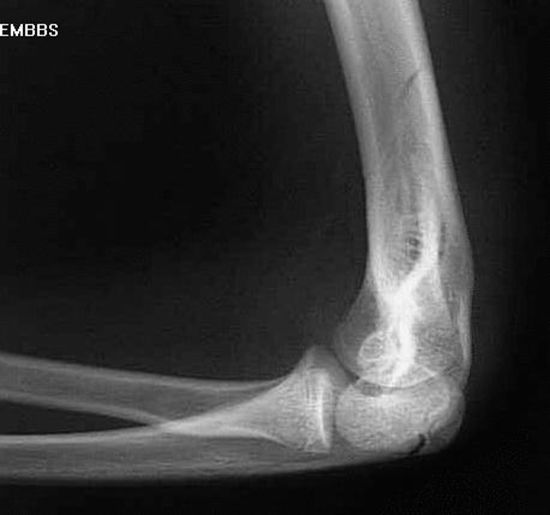

肱骨髁上骨折

肱骨髁间骨折

桡骨头骨折